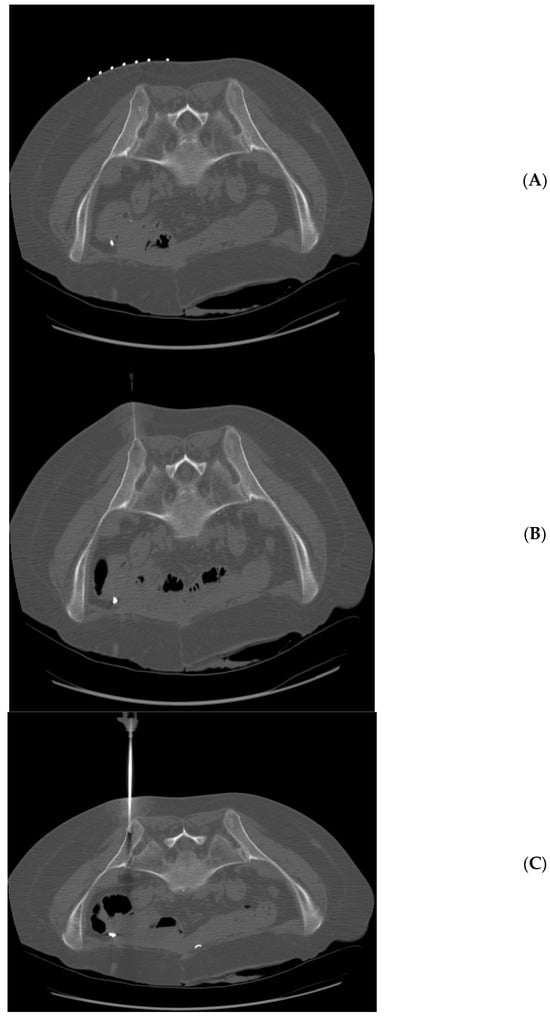

Figure 2.

65 year-old woman with multiple myeloma. Technically successful biopsy, with adequate pathology results. (A) Prone position pre-planning CT with skin guidance markers on the left side of the patient. (B) Prone position CT with biopsy needle tip approaching left posterior iliac spine. (C) Prone position CT with biopsy needle tip within the left posterior iliac spine.